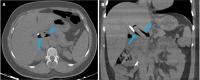

Endoscopic retrograde cholangiopancreatography (ERCP) is a cornerstone procedure for the diagnosis and management of pancreatic and hepatobiliary diseases. Although its diagnostic role has been increasingly supplanted by noninvasive imaging modalities such as magnetic resonance imaging (MRI) and magnetic resonance cholangiopancreatography, the therapeutic applications of ERCP have continued to expand. ERCP is widely used and has a generally favorable safety profile. However, it is important to recognize expected post-procedural imaging findings and serious complications that can arise. The increasing complexity of therapeutic interventions and the growing volume of procedures have led to a higher incidence of complications that often present with overlapping clinical and laboratory features, underscoring the critical role of imaging in differential diagnosis. This review focused on the typical normal ERCP findings and the imaging characteristics of common complications, including pancreatitis, bleeding, ERCP-related infections, perforations, and stent-related complications. Computed tomography (CT) is particularly valuable in timely recognition, management, and surgical decision-making for these complications. Furthermore, MRI offers a radiation-free alternative for managing complications in selected patients. Therefore, radiological modalities, particularly CT and MRI, are critical tools for the rapid diagnosis, management, and surgical decision-making processes for post-ERCP complications.